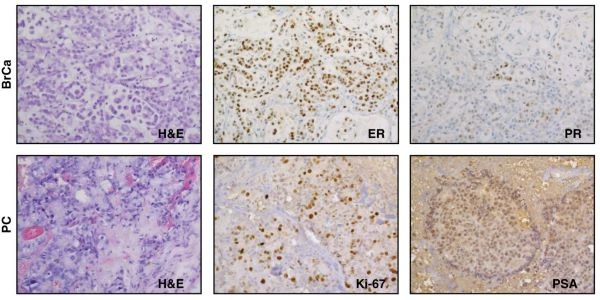

Quantification of Molecular Markers in 2-plex IHC

StrataQuest software quantified NCAM and Ki67 distribution in kidney cancer samples, demonstrating how 2-plex IHC staining can be applied to spatial analysis of tumor markers.